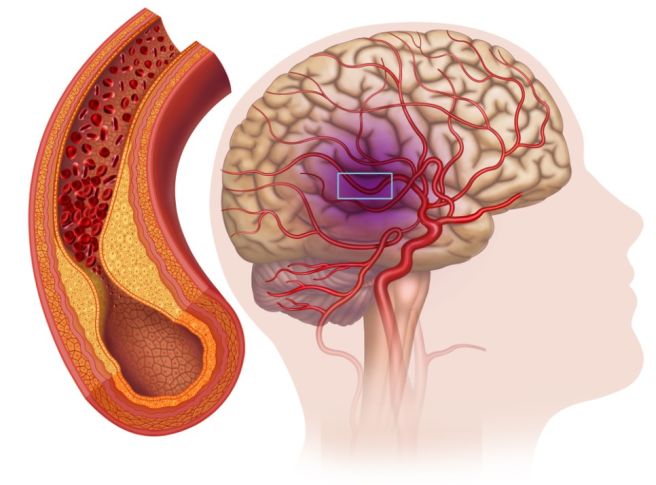

혈관의 막힘

중풍의 가장 주요한 원인 중 하나는 뇌혈관이 막히는 것입니다. 뇌로 가는 혈류가 차단되거나 줄어들면 뇌 세포에 산소와 영양분이 공급되지 않아 중풍이 발생할 수 있습니다. 특히, 동맥경화증이나 혈전이 혈관을 막는 경우 뇌졸중이나 중풍을 유발하는 주요 원인입니다.

뇌혈관에 있는 혈관벽이 약해지면 혈관이 터지거나 좁아지면서 중풍을 유발할 수 있습니다. 선천적으로 발생할 수 있으며, 고혈압이나 동맥경화와 같은 후천적인 원인으로 악화될 수 있습니다. 혈관이 약해지면 혈액이 뇌에 제대로 공급되지 않아 뇌 세포가 손상되기 쉽습니다.

고지혈증

고지혈증은 혈관에 지방이 축적되어 혈관이 좁아지고 경직되게 만듭니다. 혈액 순환에 문제가 생기고, 혈관이 막히거나 터질 위험이 커지며, 결과적으로 중풍을 일으킬 수 있습니다. 고지혈증은 종종 다른 심혈관 질환과 함께 발생하기 때문에 중풍의 중요한 위험 요소로 작용할 수 있습니다.